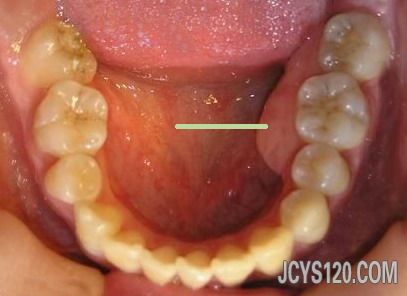

本帖最后由 喜欢 于 2013-3-7 15:38 编辑 牙槽骨是有骨刺的,但在临床上多见有骨刺区有骨尖,局部牙龈有时可见白色(压迫引起),用手按压局部有压痛,既然是牙医说的骨刺,应该由牙医解决,而不是找我们内科医生解决,浮版主说好,3 楼就说的有点过了。 1.消除有碍的骨突:牙齿拔除后由于骨质的吸收不均,常可形成骨尖或骨突。若经过一段时间后仍不消退,且有压痛,或有明显倒凹,妨碍义齿摘戴时,应进行牙槽骨修整,一般在拔牙后1个月左右修整较好。   2.骨性隆突修整术:骨隆突系正常骨骼上的骨性隆起,组织学上与正常骨组织无区别。过大的骨隆突在义齿摘戴时,引起组织破溃疼痛,严重者义齿无法戴入使用。   修复前应有充分的估计和判断,及时施行修整术。骨隆突常发生在:①下颌前磨牙舌侧,一般双侧对称,也可为单侧,其大小不一,也称为下颌隆突;②腭中缝处,呈嵴状隆起,也称为腭隆突;③上颌结节,结节过度增生形成较大的骨性倒凹。对双侧上颌结节肥大的情况,常常只需修整一侧上颌结节,解决妨碍义齿就位的问题即可。